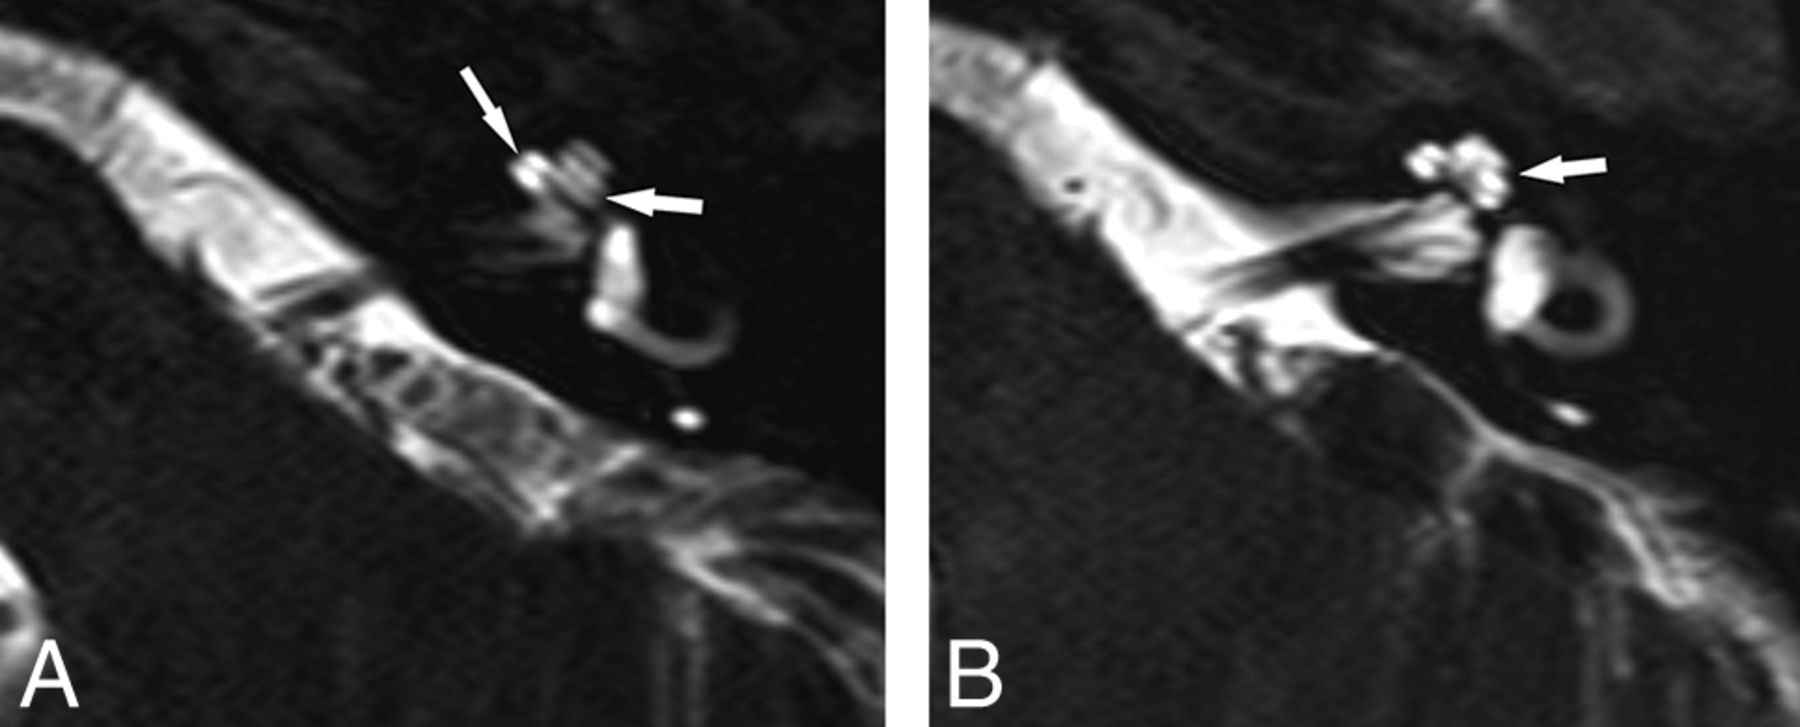

Abnormal R2 notch in 2 different IP-II malformation ears, both with profound SNHL. A–C, A shallow obtuse notch is present (arrow). The scala vestibuli is enlarged (arrowheads) with anterior bowing and high insertion of the second part of the interscalar septum. The measured angle at the same level is 132° (B) with a depth of 0.3 mm (C). D and E, In the other patient, no lateral notch is seen (arrow) and the scala vestibuli is enlarged (arrowhead). At the same level, the angle is 180° and the depth is 0 mm (E).

Most interesting, the interscalar septum in IP-II malformations is visualized on histopathology; however, it is often not seen on CT because of a higher insertion point and lack of ossification.4,12 Evaluation of the R2 notch on CT would be of value and further research into normal and abnormal values is needed. In IP-II malformation ears, the second portion of the septum bulges anteriorly and is associated with an enlarged scala vestibule, which was commonly found in our cases (Fig 4).13 In a recent study, the second part of the interscalar septum was routinely identified using a higher resolution T2 drive sequence at 3T. The authors proposed evaluating the distance between the osseous spiral lamina of the upper basal turn and the first signal void anteriorly, presumably the second part of the interscalar septum. A cutoff value of ≥1.2 mm was found useful for diagnosing the IP-II malformation.14

Seventeen ears with IP-II malformation were confirmed. Seven patients were male, and 3 were female with an age range of 0.8–6 years (mean, 2.9 years) (Fig 3). As per consensus evaluation, a displaced second portion of the interscalar septum was present in 15 ears with associated scalar asymmetry. The second portion of the interscalar septum was not identified in 2 ears. Vestibular abnormalities were present in 8 ears, typically enlargement of the vestibule with diminished size of the bone island in 8 ears and endolymphatic duct enlargement in 12 ears. The bony island was normal and the endolymphatic duct was not enlarged in any of the unilateral IP-II malformation ears (n = 3). The cochlear nerve was normal in all ears. Genetic testing was performed in only 2 patients. Connexin was normal in 1 patient, and 1 patient was heterozygous for SLC26A4 with 2 separate disease-causing mutations.